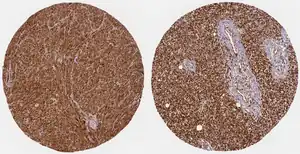

WWTR1 (TAZ) is implicated a wide variety of cancers including melanoma, head and neck squamous cell carcinoma, breast cancer, non-small cell lung cancer, and others due to its high gene and histological expression, as well as correlation with increased metastasis and poorer survival in animal studies and patient data.[9] Along with the structurally similar co-regulator YAP, many studies have described their role in promoting oncogenesis, altering neoplastic metabolism, and generating resistance to therapeutic intervention.[8][9][32][33] In particular, TAZ overexpression conferred resistance to cisplatin chemotherapy as well as immunotherapy treatment with a PD-1 antibody.[32]

| WWTR1 Protein Expression By Cancer Type (from Protein Atlas) | |||

| Cancer Type | # Samples with Medium/High Expression | Total # Patient Samples | % Patient Samples with Medium/High Expression |

| Glioma | 11 | 11 | 100% |

| Thyroid | 4 | 4 | 100% |

| Lung | 12 | 12 | 100% |

| Colorectal | 11 | 11 | 100% |

| Head and Neck | 4 | 4 | 100% |

| Liver | 12 | 12 | 100% |

| Carcinoid | 4 | 4 | 100% |

| Pancreatic | 9 | 9 | 100% |

| Urothelial | 9 | 9 | 100% |

| Prostate | 10 | 10 | 100% |

| Testis | 11 | 11 | 100% |

| Breast | 12 | 12 | 100% |

| Cervical | 9 | 9 | 100% |

| Endometrial | 10 | 10 | 100% |

| Ovarian | 11 | 11 | 100% |

| Melanoma | 12 | 12 | 100% |

| Skin | 11 | 11 | 100% |

| Stomach | 10 | 11 | 90.1% |

| Renal | 10 | 11 | 90.1% |

| Lymphoma | 9 | 12 | 75% |